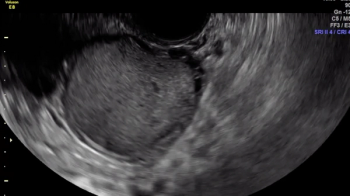

The uterine fundus is being pushed cephalad by the transvaginal ultrasound probe, eliciting smooth sliding of the uterine fundus over the bowel. Some fluid is noted within the rectouterine pouch, which often suggests a non-obliterated pouch.

In this case, there is a fixed ovary posteriorly and subtle hypoechoic nodule posterior to the uterus at the level of the internal cervical os, suggesting of deep endometriosis of the torus uterinus.